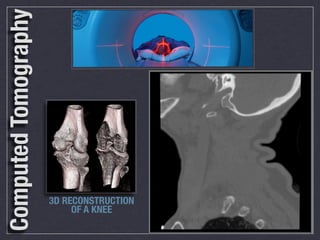

Computed Tomography

3D RECONSTRUCTION

OF A KNEE